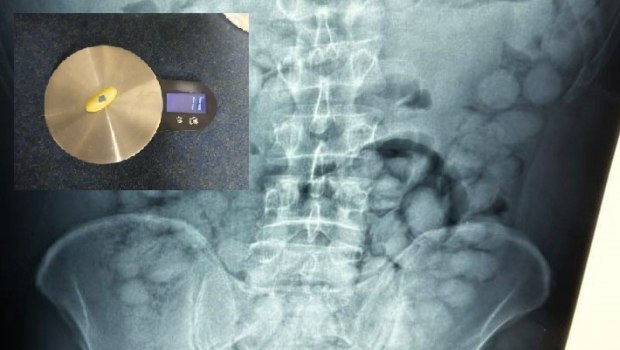

Στον έλεγχο που έγινε διαπιστώθηκε ότι είχε καταπιεί μεγάλη ποσότητα κοκαΐνης με την αστυνομία να δίνει στη δημοσιότητα τις σχετικές εικόνες που είναι χαρακτηριστικές.

Στις ακτινογραφίες διακρίνονται οι συσκευασίες που είχε καταπιεί με τους γιατρούς να εντοπίζουν 100 κάψουλες των 11 γραμμαρίων η καθεμία.

Η συγκεκριμένη μέθοδος διακίνησης ναρκωτικών είναι εξαιρετικά επικίνδυνη, αφού αν άνοιγε στο στομάχι του έστω και μία συσκευασία, σε λίγα λεπτά θα είχε πεθάνει. Σύμφωνα με τις πρώτες πληροφορίες, η συνολική ποσότητα κοκαΐνης που εντοπίστηκε ξεπερνάει το ένα κιλό.